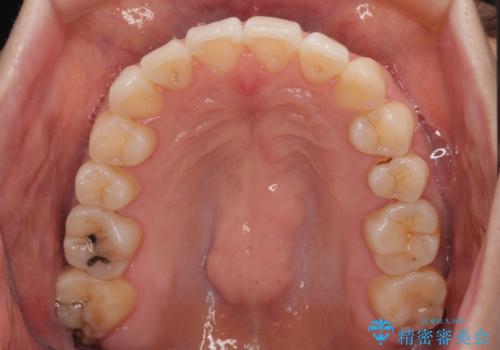

- 前歯のデコボコと、上下前歯が接触せずに前に飛び出していることを気にして来院された患者様です。

舌の突出癖が強く、それが原因で上顎歯列全体が前方に突出し、上下前歯が接触できない状態となっていました。

補助装置を用いて上顎臼歯を後方移動させ、歯列を整えながら前歯部の接触を図ることとしました。